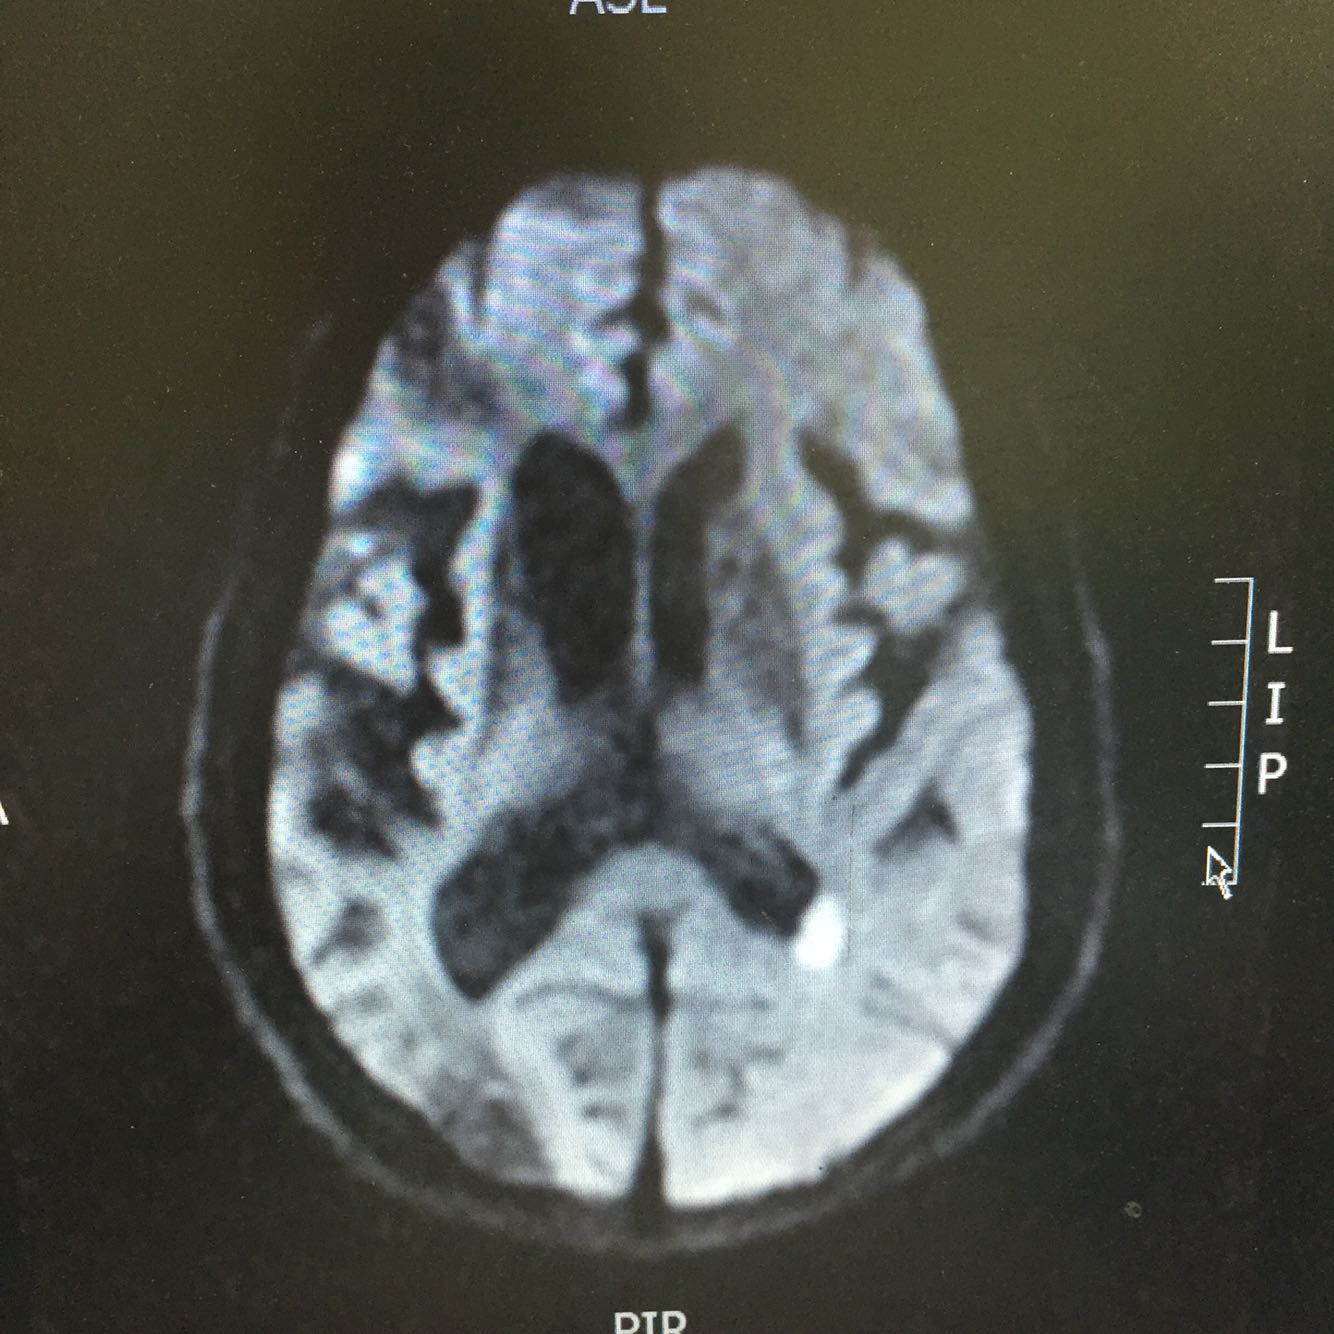

查体:血压110/70mmHg 神志清楚,言语欠流利,查体合作,双侧瞳孔等大同圆,对光反射存在,双眼活动自如,左侧鼻唇沟浅,伸舌居中,左侧肢体肌力4级,右侧肌力5级,肌张力正常,腱反射对称,双侧感觉对称,双下肢Babinski(+)Chaddock(+),颈强(-),克氏征(-) 头DWI示:左侧侧脑室后脚新发梗死。颅内多发占位性病灶,考虑转移瘤